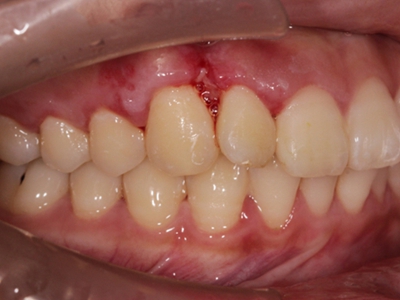

肿块有的有蒂,如息肉状;有的无蒂,基底宽广,生长较慢,但在女性妊娠期间可能迅速增大。较大的肿块可以遮盖一部分牙及牙槽突,表面可见牙压痕,易被咬伤而发生溃疡,伴发感染。随着肿块的增长,牙槽骨壁逐渐被破坏,牙可能发生松动、移位。

局部刺激因素,包括菌斑、牙石、食物嵌塞或不良修复体的刺激,引起局部长期慢性炎症,致使牙龈结缔组织形成反应性增生物,即牙龈瘤。此外,牙龈瘤可能和内分泌有关,妇女怀孕期间容易发生牙龈瘤,而分娩后会缩小或停止生长。

对于牙龈瘤可在局麻下手术切除,切除必须彻底,否则易复发。如果复发,仍可手术切除。多次复发者,即使病变波及的牙无松动,也应将牙拔除,防止再发。